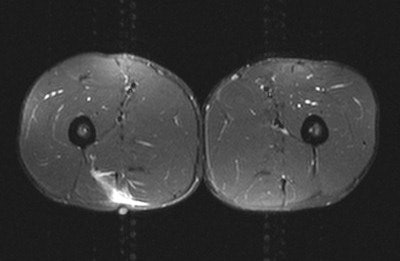

Un esprínter de 28 años sintió comienzos de dolor en la parte posterior de la pierna durante una carrera. Había evidencia de hinchazón, dolor y fuerza reducida. Una imagen por RM demostró un esguince miotendinoso grado II en la porción larga del músculo bíceps y un esguince miotendinoso grado I en el músculo recto del fémur derecho asociado con cicatriz del tendón central. Los indicadores de pronóstico fueron la longitud craniocaudal, porcentaje de participación del área transversal del músculo, presencia de una cicatriz asociada y desgarros distales versus proximales. El diagnóstico clínico fue un esguince del tendón de la corva. Todas las imágenes son cortesía del Dr. Jeremiah C. Healy.Alrededor de 10.000 atletas provenientes de 205 países participarán en los Juegos Olímpicos de Londres, y a ellos se sumarán 11.000 entrenadores, oficiales y miembros del COI, dijo O’Connor durante una sesión especial que tuvo lugar en el Congreso de Radiología del Reino Unido (UKRC) en la ciudad de Manchester. Además, otros 4.000 atletas participarán en los Juegos Paraolímpicos. En comparación, los últimos Juegos de Invierno en Vancouver atrajeron a unos 2.500 atletas.